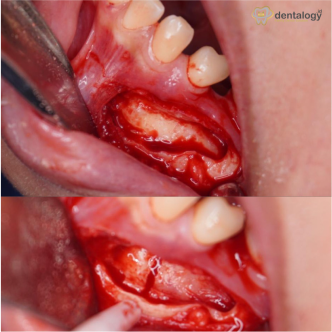

Before dan After pencabutan gigi di dentalogy